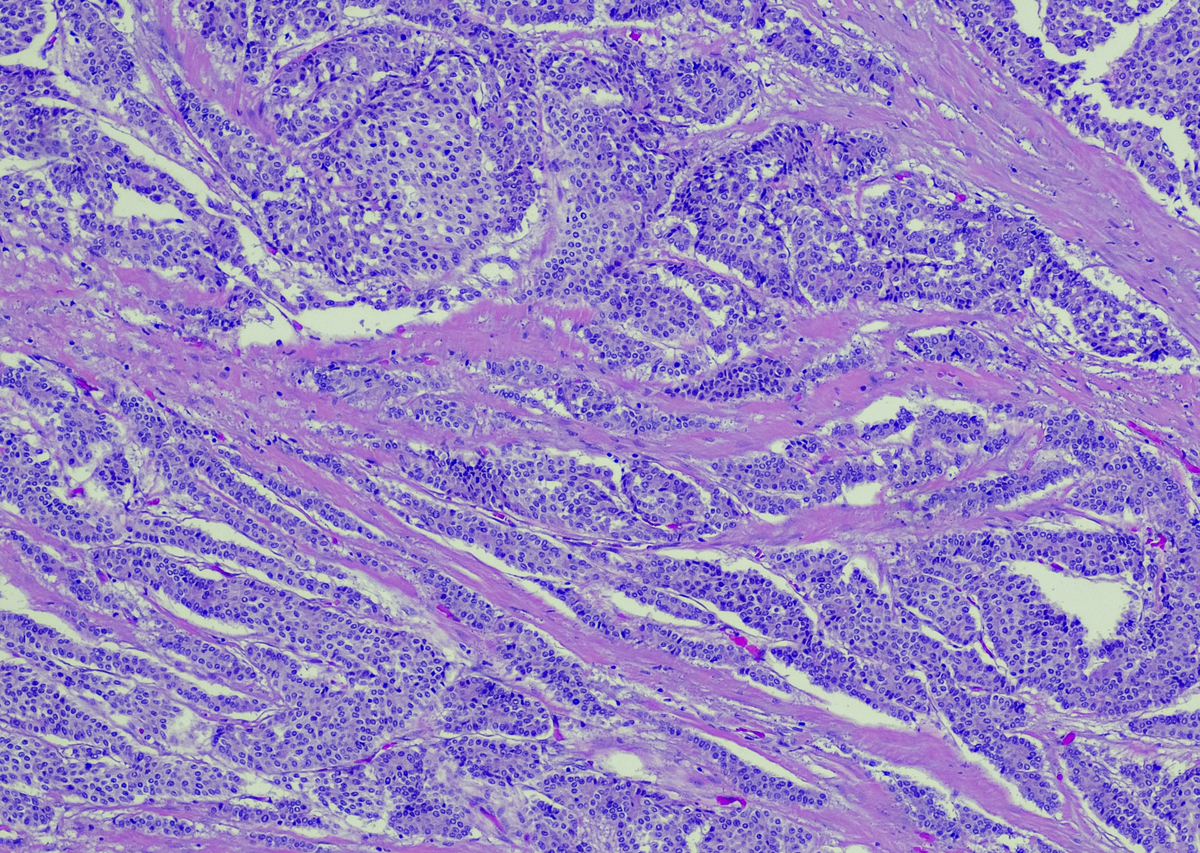

对乳腺肿瘤进行分割的结果是将乳腺肿瘤从周围正常组织中分离出来,形成一个独立的区域。这个区域可以被用于进一步的研究和处理,例如分析肿瘤的形态学特征和生物学特性,制定个性化治疗方案等。乳腺肿瘤分割的精度和效果取决于使用的算法和技术,以及影像质量和肿瘤的大小、位置和形态等因素。